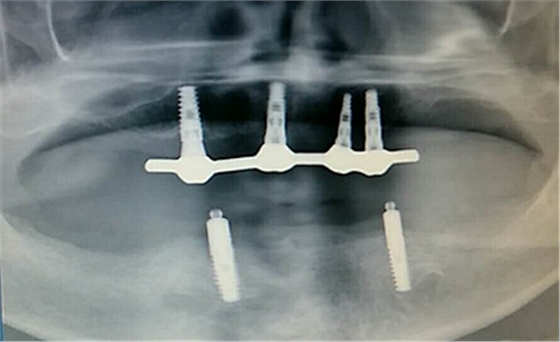

毛國(guó)斌種植病例——群討論分享